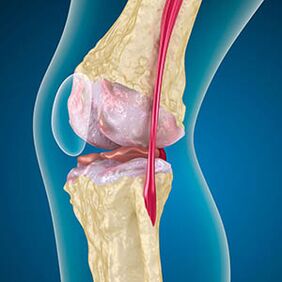

Bei Arthrose ist der Knorpel, der die Ränder der Knochen auskleidet, eine Abrieb oder fehlend. Beschädigtes Gewebe ist keine Schmerzquelle, da es keine Rezeptoren hat. Entzündungen in nahe gelegenen Strukturen verursachen charakteristische Symptome.

Der Körper setzt die Regeneration von beschädigten Geweben fort, aber der Knorpel wächst ungleichmäßig. Infolgedessen werden Unregelmäßigkeiten gebildet, die andere Elemente des Gelenks verletzen. Die Art der Osteophyten wird durch Entschädigung für glatte Gelenkknorpel erklärt. Eine andere Version zeigt, dass das Wachstum von "Spurs" Es ist mit dem Versuch verbunden, das Gelenk medial oder lateral aufgrund der Muskelschwächung zu stabilisieren.